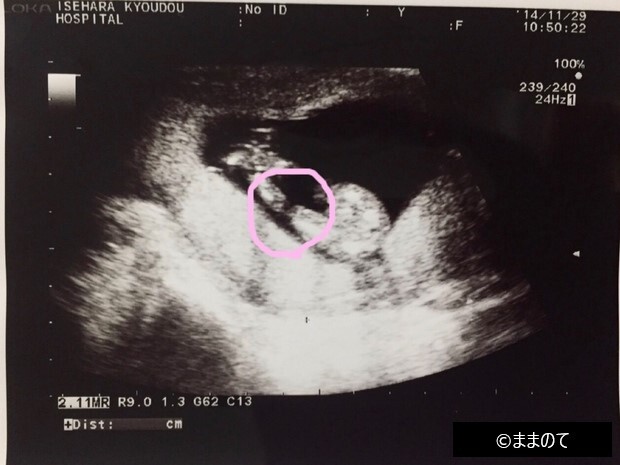

【女の子のエコー】妊娠14週

上の画像は、赤ちゃんの股を下から見ている構図です。丸印で囲んだ部分が割れ目に見えることから「女の子の可能性が高い」と医師から伝えられたそうです。妊娠14週では形成段階の外性器ですが、赤ちゃんの向きや体勢によっては、性別が判明することもあります。